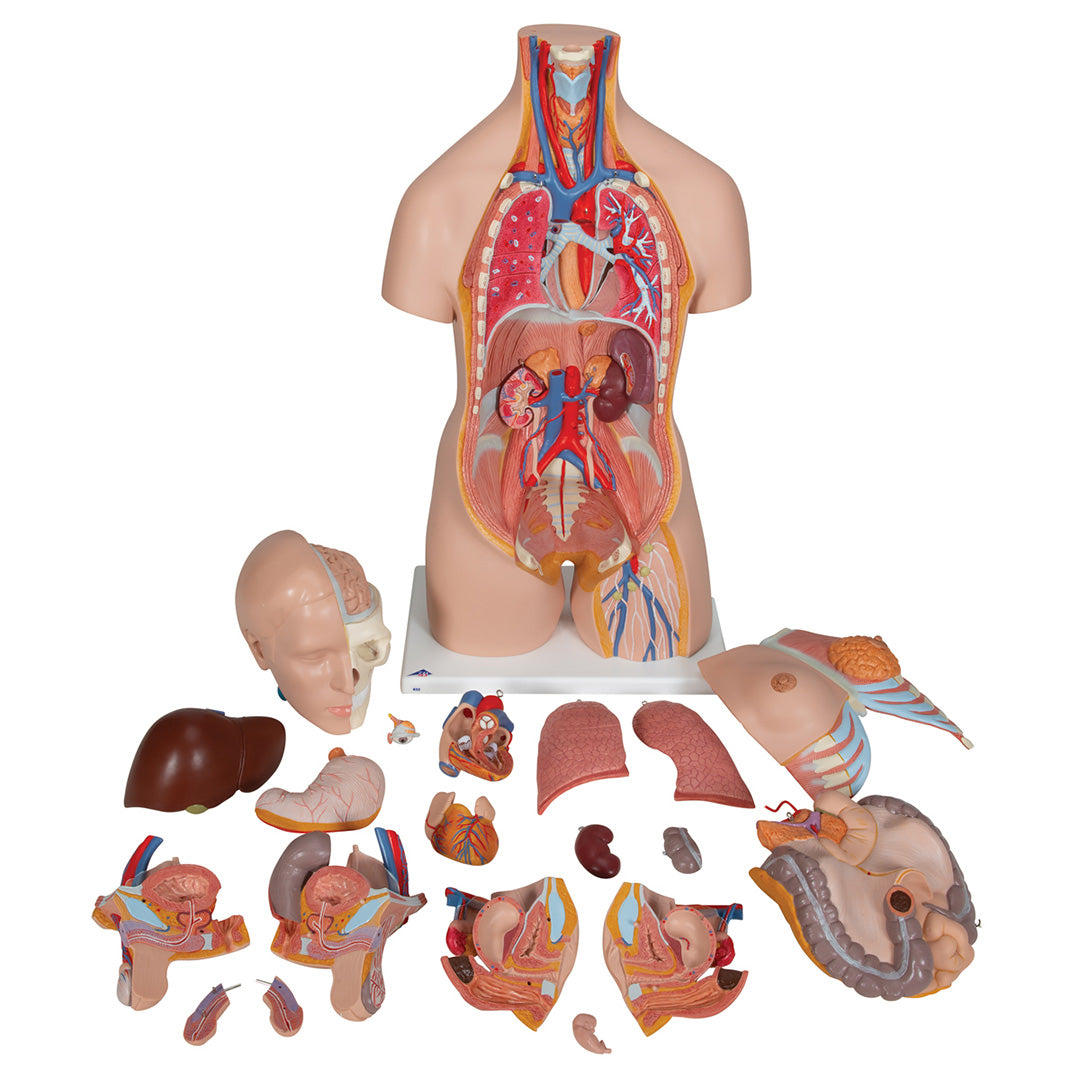

Torso de lujo de doble sexo, 20 partes

Torso de lujo de doble sexo, 20 partes

Sobre la anatomía interna humana.

Es desmontable en:

• Cabeza en 2 partes

• Cubierta torácica femenina

• 2 lóbulos pulmonares

• Corazón en 2 partes

• Estómago

• Hígado con vesícula biliar

• Paquete intestinal en 2 partes

• Mitad anterior del riñón

• Órganos genitales femeninos con embrión, en 3 partes

• Órganos genitales masculinos en 4 partes

Características

Peso 9.249 kg.

Dimension 87 x 38 x 25 cm